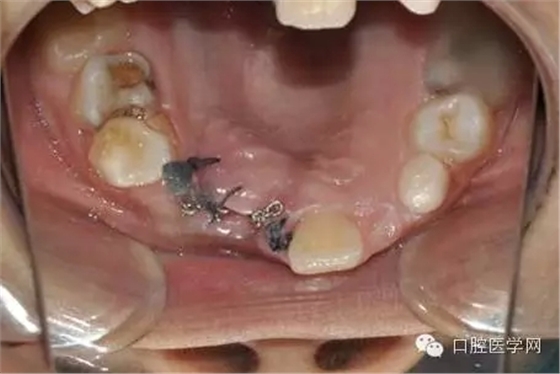

大量生理鹽水沖洗:

縫合后,要把鏈子留到外邊:

一周后拆線 :

術前已經給小孩取了牙模,所以就開始

“活動可調、釣魚式牽引器”的制作。(后續(xù)的博客會詳細的給大家講一下制作要領,和各種卡環(huán)變異的彎制。簡簡單單的彎制卡環(huán)可以完勝各種焊接或鑄造。 )

帶入口內調整吊桿方向加輕力:

(咬合調整好,加輕力激活)

每周復診:清洗,加力,適當調整吊桿方向

用時9周完成埋伏牙牽引。